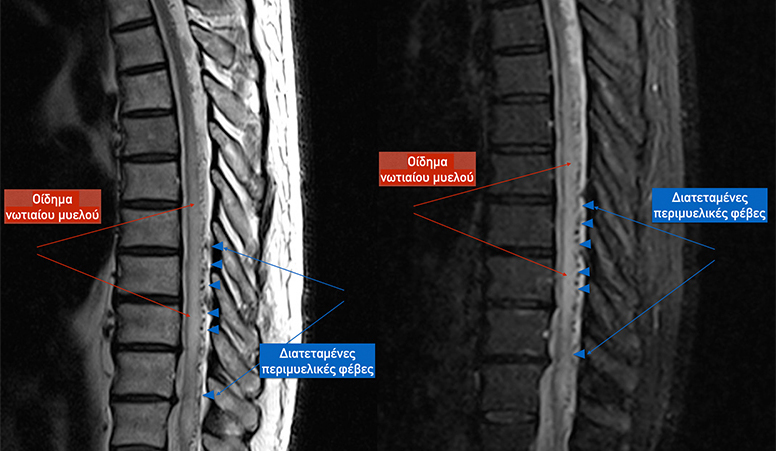

Ωστόσο η μαγνητική τομογραφία, αγγειογραφία επιτρέπουν σήμερα την διάγνωση των SCDAVF με ακρίβεια σε όλες τις περιπτώσεις. Επιπρόσθετα η μαγνητική τομογραφία αποκαλύπτει την παρουσία οιδήματος ή γλοιώσεως, παρέχοντας πληροφορίες γιά την έκταση της βλάβης του παρεγχύματος του μυελού. Ωστόσο αρνητική μαγνητική τομογραφία και αγγειογραφία δέν αποκλείουν 100% την παρουσία SCDAVF και η κλασσική ενδαρτηριακή ψηφιακή αγγειογραφία είναι απαραίτητη σε κάθε κλινική υποψία.